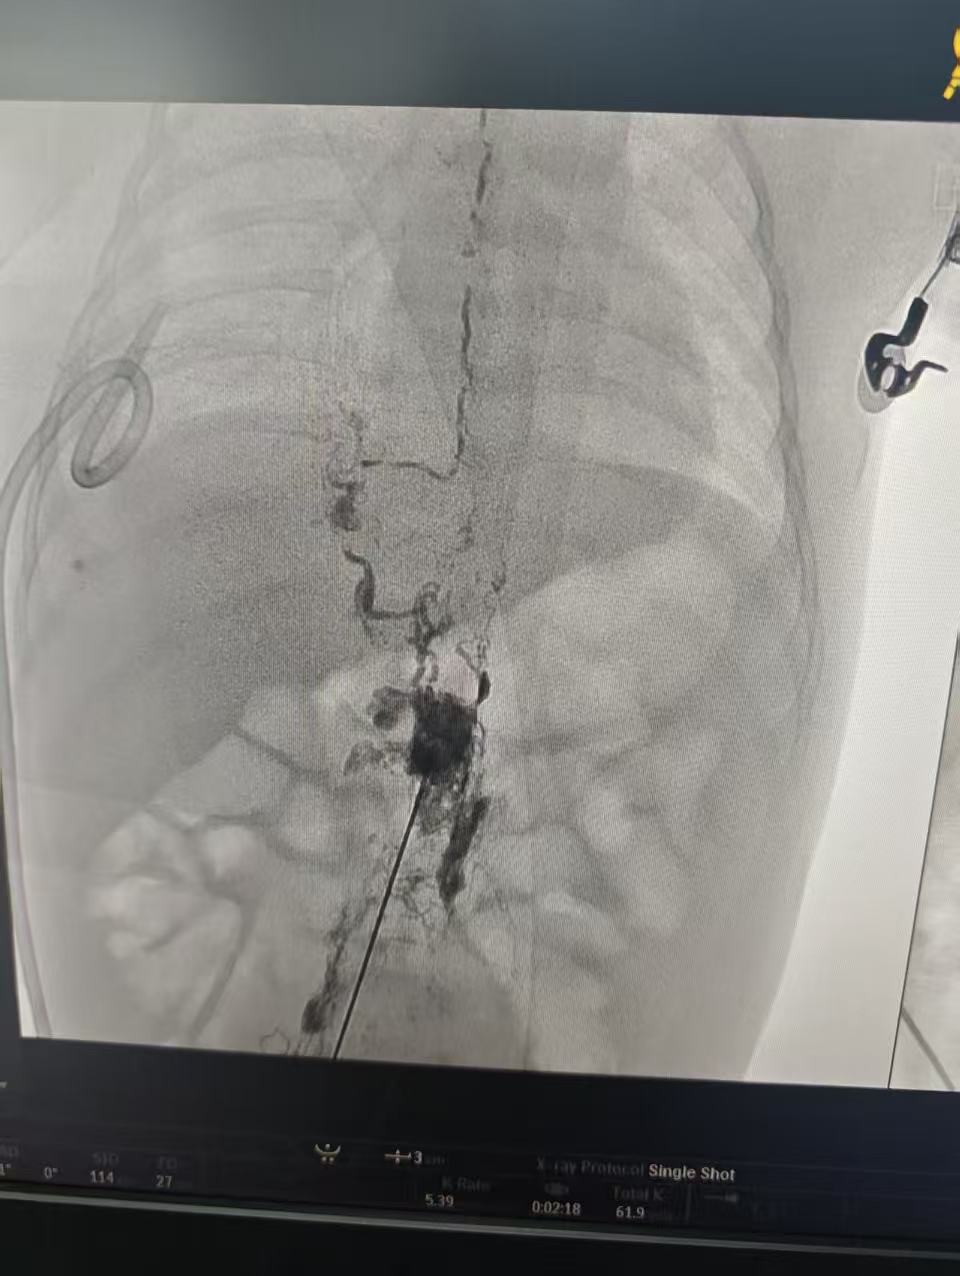

一切准备就绪后,小诺接受手术。血管介入科黄文雅主任团队在超声及影像引导下,经腹股沟淋巴管穿刺,注入造影剂清晰显示胸导管走行及漏口。面对比发丝还纤细的淋巴管,手术团队凭借精湛技艺,将封堵剂精准注入漏口,既彻底阻断乳糜液异常渗漏,又最大程度保留正常淋巴循环。术中麻醉手术科团队针对 2月婴儿的生理特点,制定精细化麻醉方案,精准调控麻醉深度。手术全程历时数小时,精准完成淋巴管造影与瘘口封堵。目前,小诺术后恢复良好,乳糜液引流量已显著减少,呼吸顺畅,营养吸收逐步改善,正在接受后续康复护理,即将顺利出院。

术中精准定位